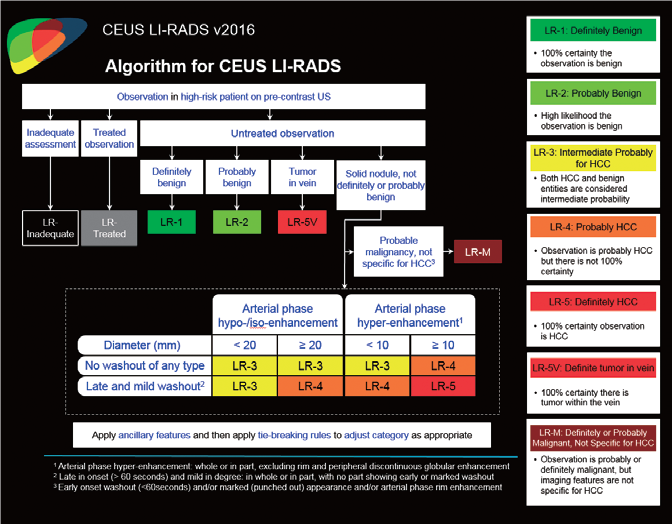

Малюнок 6. Алгоритм та класифікація CEUS LI-RADS®

LI-RADS 5 ГЦК

У 63-річної жінки з алкогольним цирозом печінки виявлено ураження печінки розміром 3 см. Межа ізоехогенного ураження та його гіпоехогенний ореол може бути чітко відображений на сірошкальному зображенні. За допомогою кольорового доплера можна виявити внутрішньопухлинну судинну структуру. Багата судинна структура може бути окреслена за допомогою SMI, та можуть бути показані викривлені судини, що свідчить про злоякісне ураження. Після ін'єкції контрасту, в артеріальній фазі, ураження демонструє гомогенне гіперпосилення, пов'язане з підживлюючими судинами. Вимивання не спостерігається на 1 хвилині і на 2 хвилині. У відстроченій фазі на 3,5 хвилині можна спостерігати помірне вимивання. Вимивання повільно прогресує і стає більш чітким на 5 хвилині. Пізнє (≥ 60 сек) і помірне вимивання є однією з основних ознак LI-RADS 5 і є дуже важливим для диференціації від LI-RADS M, який показує раннє (<60 сек) і/або виражене вимивання. В результаті ураження класифікується як CEUS LI-RADS 5. Класифікація CEUS LI-RADS відповідає LI-RADS на КТ.

Оцінка результатів лікування ГЦК

LI-RADS 4 множинні ГЦК

Це випадок 60-річної жінки з декомпенсованим цирозом печінки з асцитом. На сірошкальному зображенні можна виявити два вогнищевих ураження, розміром 21 мм і 10 мм відповідно, розташовані в сегменті 5. Оскільки дослідження методом зсувної хвилі на апараті Canon виконується штовхаючим імпульсом, пацієнтам з асцитом не можна проводити дослідження за допомогою зсувної хвилі, для визначення стадії фіброзу. На ранній артеріальній стадії гомогенне гіперехогенне підсилення спостерігається в обох ураженнях. Ураження є ізоехогенними в портальній венозній та пізній фазах, вимивання не спостерігається через 6 хвилин після ін'єкції, тому ці ураження були класифіковані як LI-RADS 4, ймовірна ГЦК. Важливо знати, що LI-RADS 5 - це ГЦК зі 100% вірогідністю, і вона не потребує біопсії. Значна кількість LI-RADS M (ймовірно або точно злоякісні, але не специфічні для ГЦК) і LI-RADS 4 (ймовірна ГЦК) насправді являються ГЦК.

LI-RADS 5 з декількома ГЦК

У 70-річної жінки з цирозом печінки, хворої на вірусний гепатит С, у правій частці печінки виявлено вогнище ураження розміром 23 мм. Детальна судинна структура та підживлююча судина чітко візуалізуються за допомогою CEUS на ранній артеріальній фазі та під час портальної венозної фази, а ураження є ізопідсилюючим. Це ураження є типовим для LI-RADS 5 за своїм розміром, гіперпосиленням в артеріальній фазі та пізнім і помірним вимиванням, що спостерігається через 3 хвилини після ін'єкції.

Покращена тканинна супресія забезпечує точну і швидку діагностику при диференціації злоякісності вогнищевого ураження печінки, і CEUS LI-RADS® може точно діагностувати категоризацію. Діагностична ефективність і продуктивність значно покращуються завдяки високій якості зображення. Крім того, нещодавно розроблені інтерфейс і дизайн системи забезпечують відмінну ергономіку для користувачів.